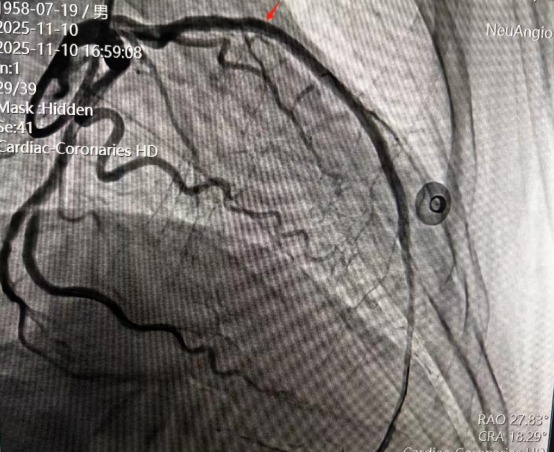

术后造影

·术后优化:在球囊扩张并植入支架后,团队再次利用IVUS对结果进行了“质检”。通过评估支架的贴壁情况、扩张是否充分以及是否完全覆盖病变,确保了支架植入的“完美无瑕”,从根源上降低了术后再狭窄和血栓形成的风险。

最终,手术取得圆满成功,患者血管血流恢复通畅,术后恢复良好,目前已顺利康复出院。